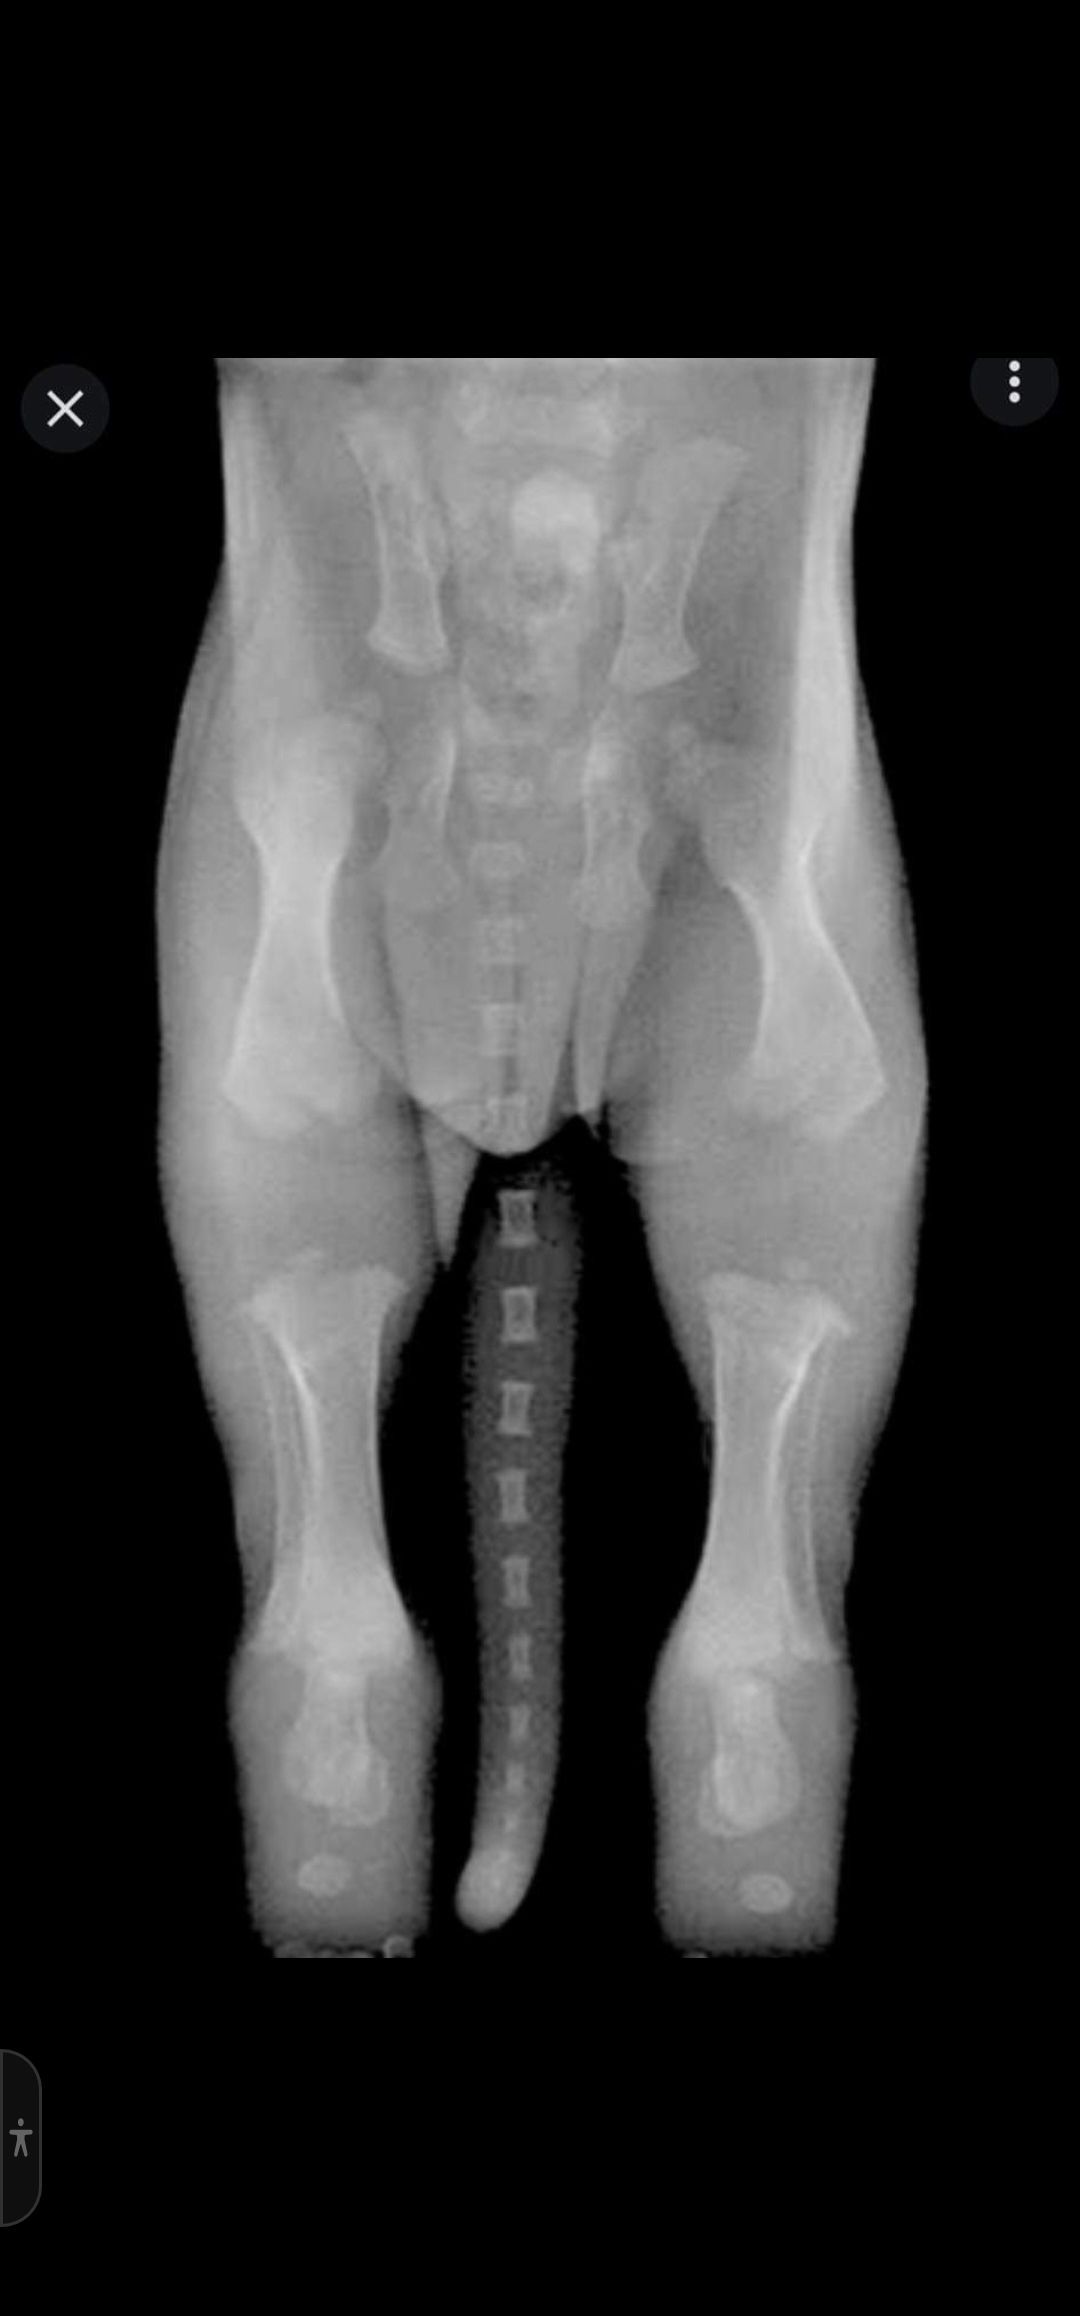

Bild 2 Junghund 6 Monate, die Knochen sind nun zusammen gewachsen